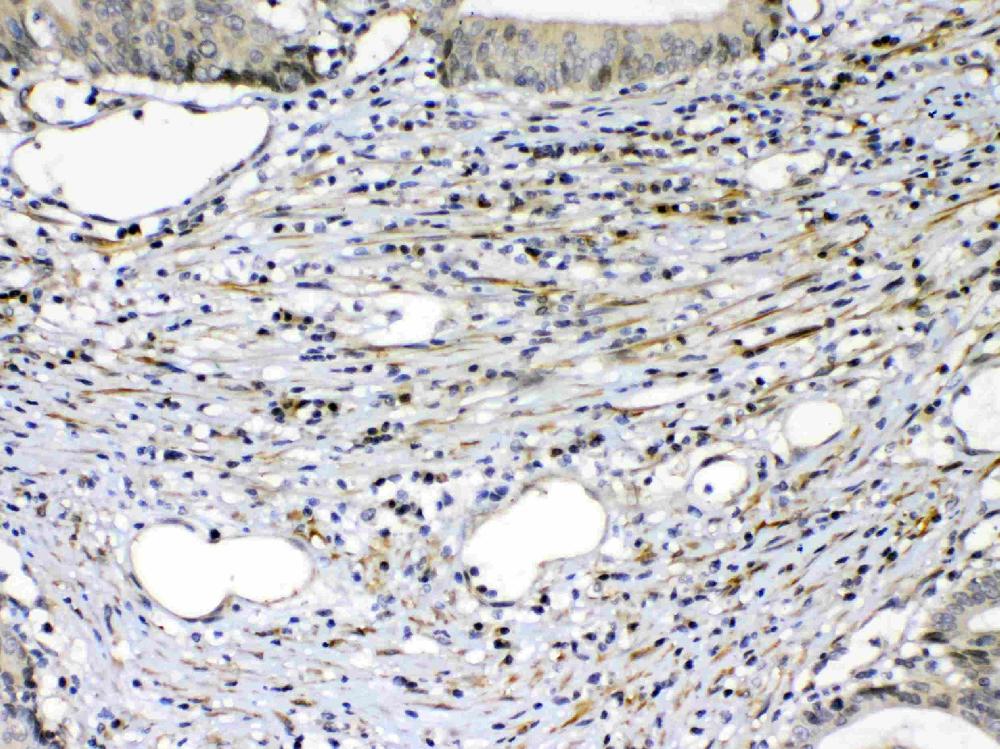

IHC analysis of VEGFR2/KDR using anti-VEGFR2/KDR antibody (A00901-2).

VEGFR2/KDR was detected in a paraffin-embedded section of human intestinal cancer tissue. Biotinylated goat anti-rabbit IgG was used as secondary antibody. The tissue section was incubated with rabbit anti-VEGFR2/KDR Antibody (A00901-2) at a dilution of 1:200 and developed using Strepavidin-Biotin-Complex (SABC) (Catalog # SA1022) with DAB (Catalog # AR1027) as the chromogen.